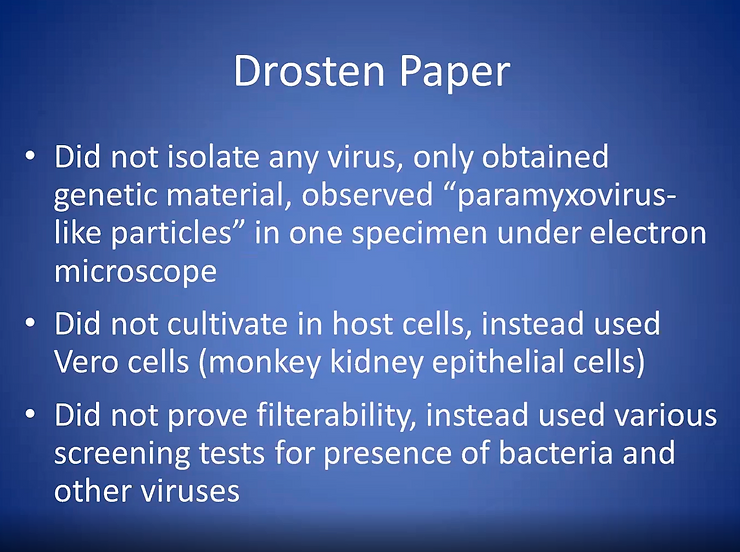

SUMMARY CATALOGUE OF ERRORS FOUND IN THE CORMAN-DROSTEN PAPER CONCERNING RTPCR TESTING FOR the SARS-CoV-2 Renamed as SARS-CoV-19 Virus

The Corman-Drosten paper contains the following specific errors:

1. There exists no specified reason to use these extremely high concentrations of primers in this protocol. The described concentrations lead to increased nonspecific bindings and PCR product amplifications, making the test unsuitable as a specific diagnostic tool to identify the SARS-CoV-2 virus renamed as SARS-CoV-19 virus.

2. Six unspecified wobbly positions will introduce an enormous variability in the real world laboratory implementations of this test; the confusing nonspecific description in the Corman-Drosten paper is not suitable as a Standard Operational Protocol making the test unsuitable as a specific diagnostic tool to identify the SARS-CoV-2 virus renamed as SARS-CoV-19 virus.

3. The test cannot discriminate between the whole virus and viral fragments. Therefore, the test cannot be used as a diagnostic for intact (infectious) viruses, making the test unsuitable as a specific diagnostic tool to identify the SARS-CoV-2 virus renamed as SARS-CoV-19 virus and make inferences about the presence of an infection.

4. A difference of 10° C with respect to the annealing temperature Tm for primer pair1 (RdRp_SARSr_F and RdRp_SARSr_R) also makes the test unsuitable as a specific diagnostic tool to identify the SARS-CoV-2 virus renamed as SARS-CoV-19 virus

5. A severe error is the omission of a Ct value at which a sample is considered positive and negative. This Ct value is also not found in follow-up submissions making the test unsuitable as a specific diagnostic tool to identify the SARS-CoV-2 virus renamed as SARS-CoV-19 virus

6. The PCR products have not been validated at the molecular level. This fact makes the protocol useless as a specific diagnostic tool to identify the SARS-CoV-2 virus renamed as SARS-CoV-19 virus

7. The PCR test contains neither a unique positive control to evaluate its specificity for SARS-CoV-2 nor a negative control to exclude the presence of other coronaviruses, making the test unsuitable as a specific diagnostic tool to identify the SARS-CoV-2 virus renamed as SARS-CoV-19 virus.

8. The test design in the Corman-Drosten paper is so vague and flawed that one can go in dozens of different directions; nothing is standardized and there is no SOP. This highly questions the scientific validity of the test and makes it unsuitable as a specific diagnostic tool to identify the SARS-CoV-2 virus renamed as SARS-CoV-19 virus.

9. Most likely, the Corman-Drosten paper was not peer-reviewed making the test unsuitable as a specific diagnostic tool to identify the SARS-CoV-2 renamed as SARS-CoV-19 virus.

10. We find severe conflicts of interest for at least four authors, in addition to the fact that two of the authors of the Corman-Drosten paper (Christian Drosten and Chantal Reusken) are members of the editorial board of Eurosurveillance. A conflict of interest was added on July 29 2020 (Olfert Landt is CEO of TIB-Molbiol; Marco Kaiser is senior researcher at GenExpress and serves as scientific advisor for TIB-Molbiol), that was not declared in the original version (and still is missing in the PubMed version); TIB-Molbiol is the company which was “the first” to produce PCR kits (Light Mix) based on the protocol published in the Corman-Drosten manuscript, and according to their own words, they distributed these PCR-test kits before the publication was even submitted;[5] further, Victor Corman & Christian Drosten failed to mention their second affiliation: the commercial test laboratory “Labor Berlin”. Both are responsible for the virus diagnostics there [6] and the company operates in the realm of real time PCR-testing.

In light of our re-examination of the test protocol to identify SARS-CoV-2 and renamed as SARS-CoV-19 described in the Corman-Drosten paper we have identified concerning errors and inherent fallacies which render the SARS-CoV-2 PCR test useless.[7][8][9][10]